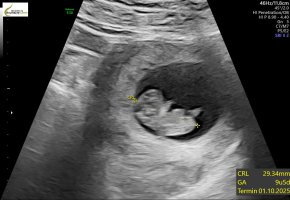

9+0, 178 bpm og 2,3cm lang. Perfekt liten miniatyrbaby som danset for oss på skjermen!

Vært så nervøs de to siste dagene pga brun utflod og lette kramper. Jordmor fant ingen synlig årsak, og konkluderte med at det mest sannsynlig kom av at morkaken tok over for plommesekken.